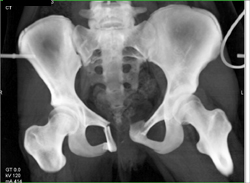

Femur Fracture